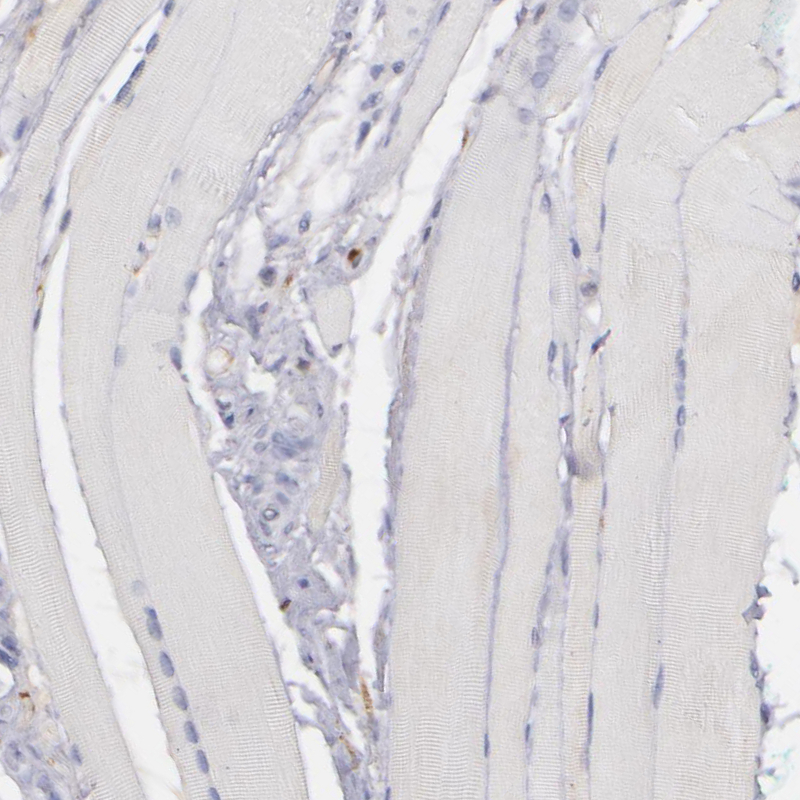

Immunohistochemical staining of human placenta shows strong positivity in plasma.